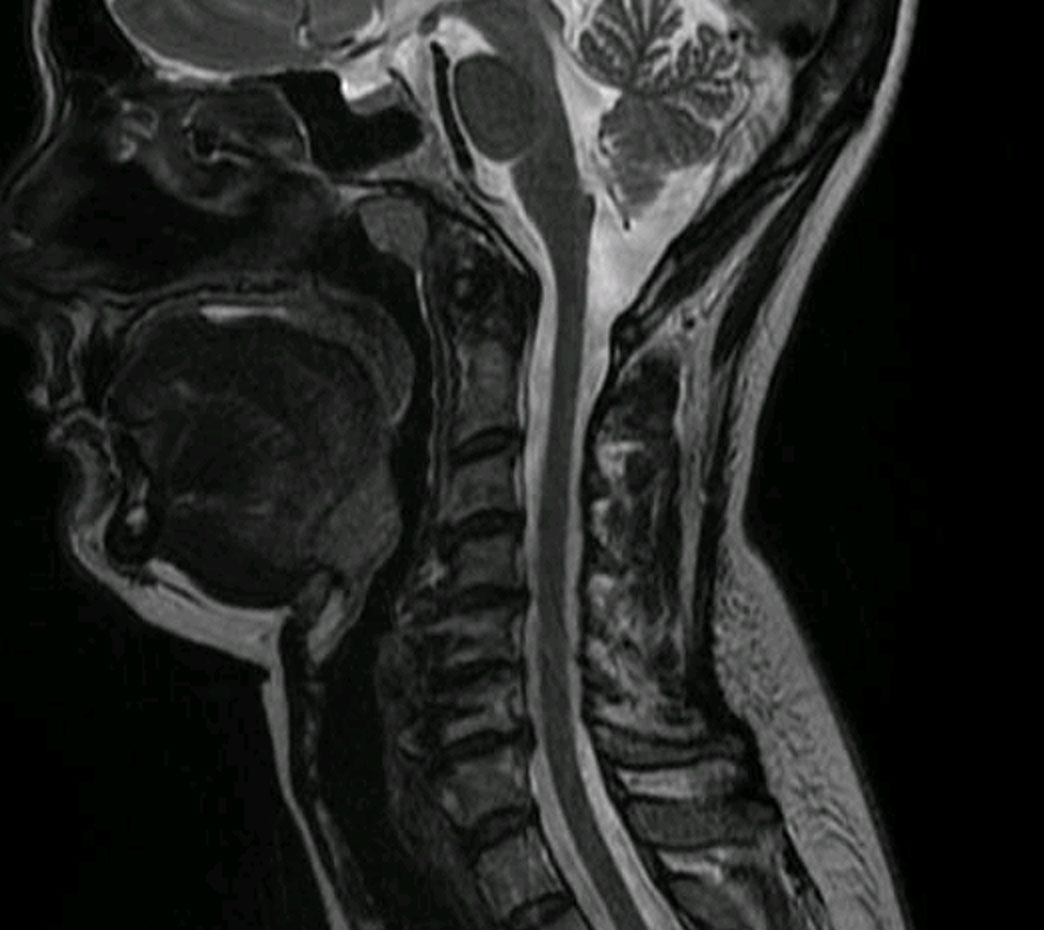

Tras hacer un estudio de la paciente mediante TAC y resonancia magnética llegamos a la conclusión que la paciente presentaba un cuadro de seudo artrosis.

Estas vertebras, al igual que los segmentos adyacentes empiezan a tener cambios degenerativos y crecimiento de los osteocitos que empiezan a comprimir el tejido neurológico.

Resonancia magnetica cervical caso real